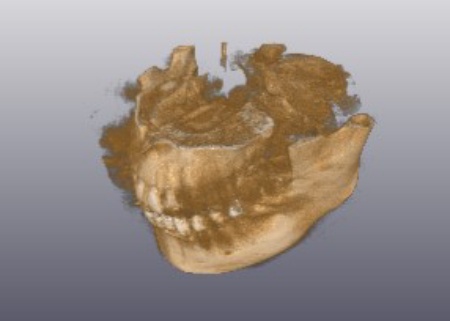

2ヶ月後に傷口がしっかりとふさがったことを確認できたため、CTを撮影してインプラントの治療計画を立て、後日インプラントを埋め込む手術を行いました。

手術の際、インプラントを埋め込む骨の中に抜歯後の傷が修復される過程でできた肉芽組織が見られたため、手術時に専用の器具を用いて取り除いてからインプラントを埋め込み、縫合しました。

完成した被せ物はネジで固定するスクリューリテインという方法を採用してしっかりと取り付け、噛み合わせに問題がないことを確認して、治療を終了しました。

治療後